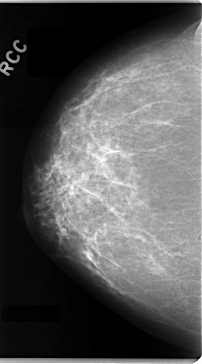

C_0089_1.RIGHT_CC

FILE: C_0089_1.LEFT_CC.OVERLAY

TOTAL_ABNORMALITIES 1

ABNORMALITY 1

LESION_TYPE MASS SHAPE IRREGULAR MARGINS SPICULATED

ASSESSMENT 5

SUBTLETY 5

PATHOLOGY MALIGNANT

TOTAL_OUTLINES 1

BOUNDARY